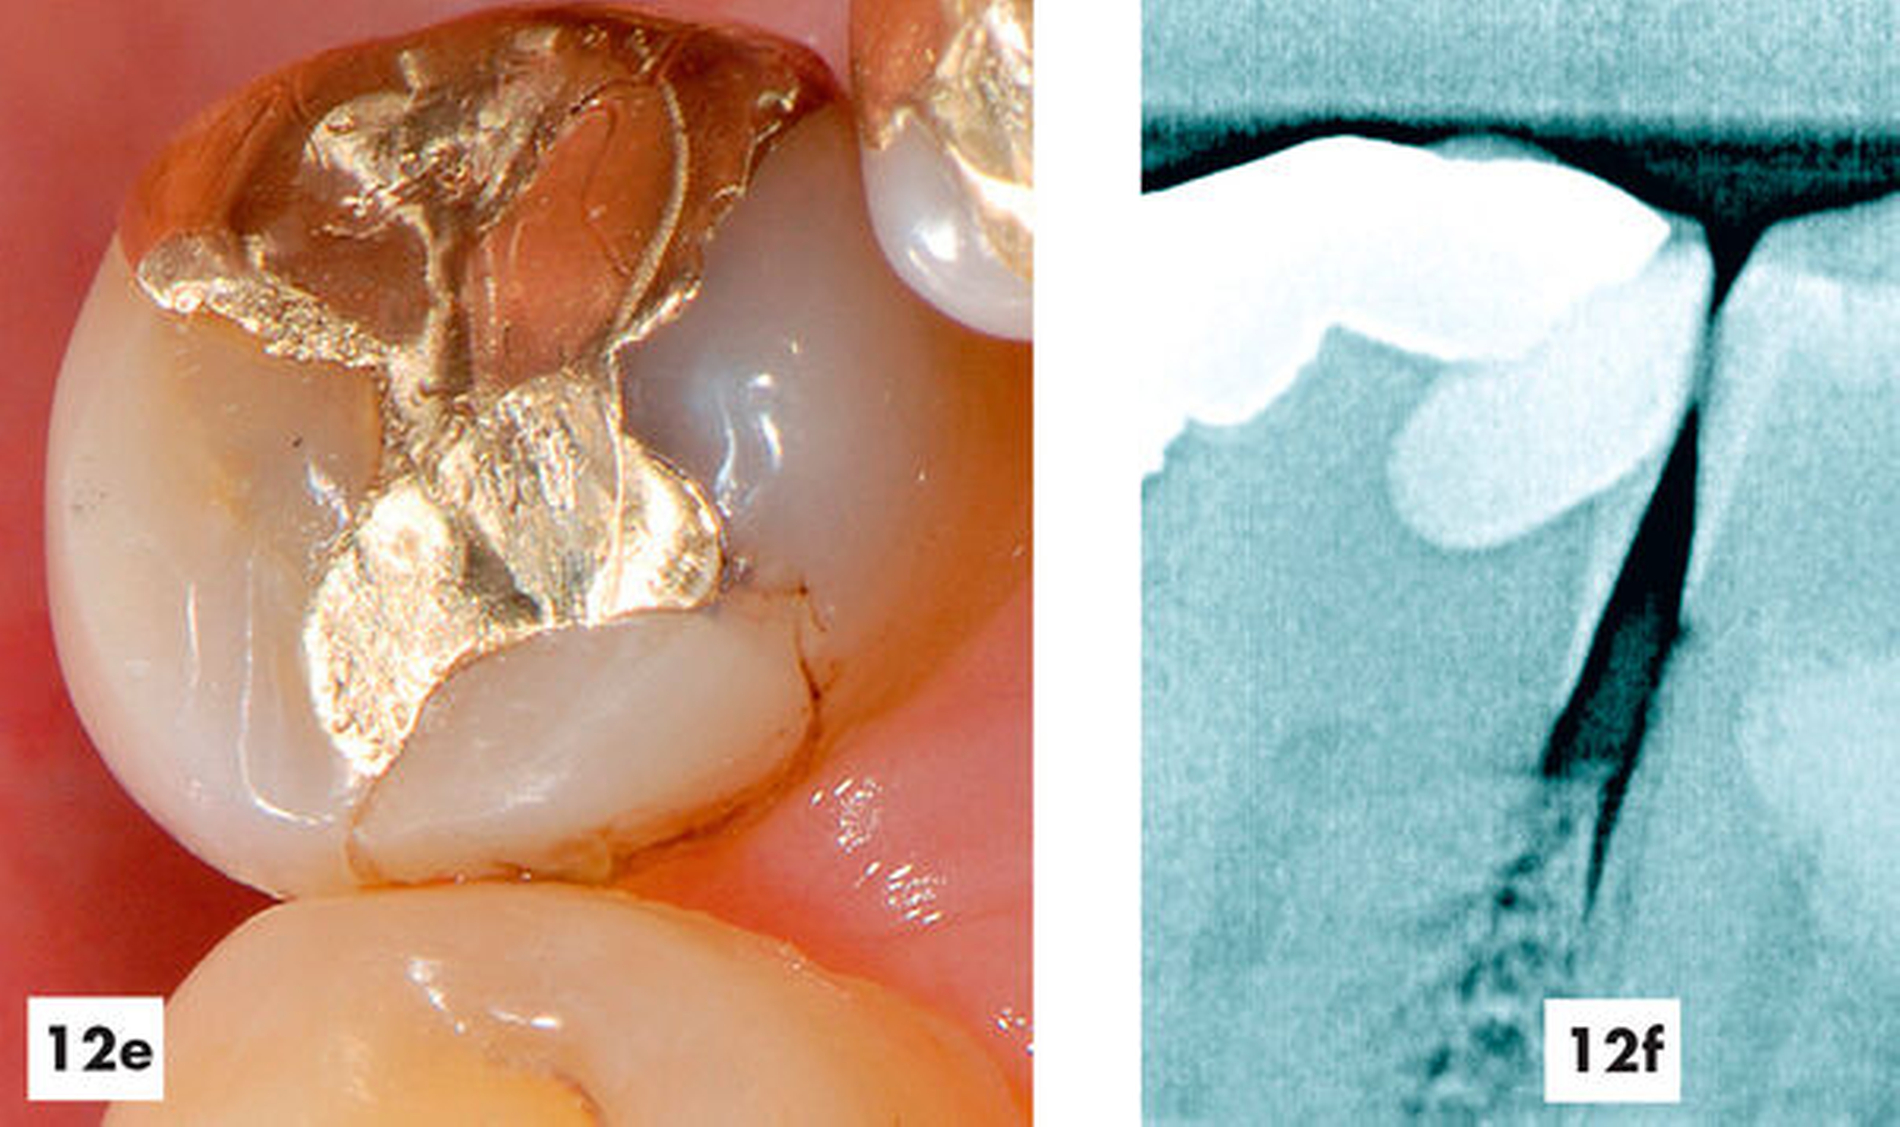

Reine Gussmetallrestaurationen

Gussmetallrestaurationen zählen nach wie vor zu den langlebigsten Versorgungen, die wir kennen. Aber auch hier kann es zu Abplatzungen, Perforationen oder Randkaries kommen. In den Abbildungen 10 bis 12 wird ein 54-jähriger Patient mit einem etwa 25 Jahre alten Gusmetall-Inlay vorgestellt, an dessen Rand ein kariöser Defekt eingetreten war. Die daraufhin eingebrachte Reparaturrestauration erfüllt seit inzwischen 22 Jahren ihren Zweck, so dass die Gesamtüberlebenszeit momentan bei fast 50 Jahren liegt.

Abbildungen 10–12: Nachbeobachtung und Reparatur eines 25 Jahre alten Gussmetall-Inlays über einen Zeitraum von 22 weiteren Jahren

Ausgangssituation

Reparatur-Restauration

Kontrolle nach 22 Jahren